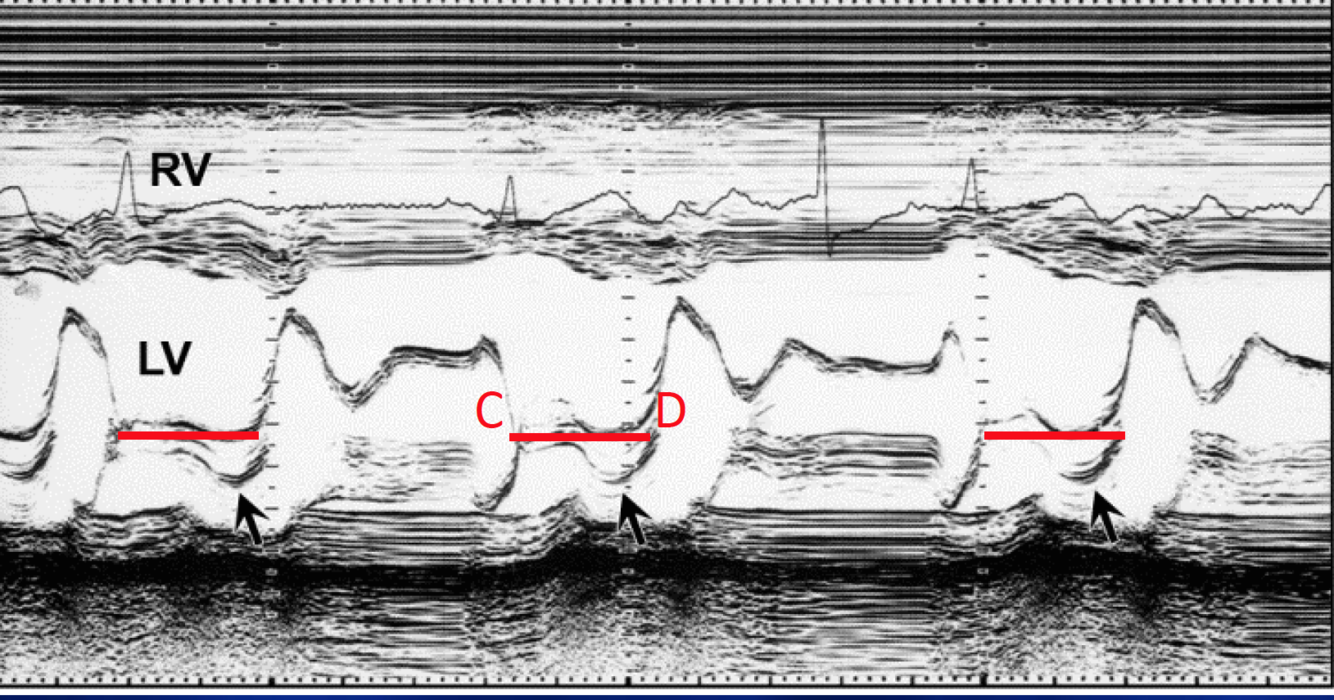

Diagnosis?

DCM

(Large E-point Septal Separation (EPSS))

E-point Septal Separation above which is abnormal (suggesting DCM). When is EPSS not valid?

>10mm

not valid with valvular dz like MS/AR.